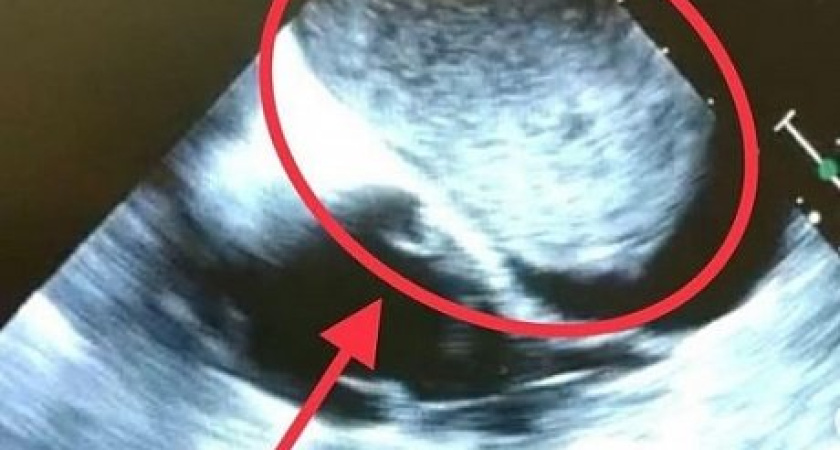

У жителя автограда опухоль выросла в сердце, что является большой редкостью. На плановое обследование к эксперту БСМП в области УЗИ сердца - заведующей отделения функциональной диагностики поступил пациент. Его беспокоили неоднократные потери сознания и перебои в работе сердца. На экране монитора сотрудники увидели необычную картину - одну из четырёх камер сердца практически полностью заполняла опухоль диаметром 10 см. Она как пробка перекрывала поток крови. Нужно было быстро принимать решение. Известный своими уникальными и сложными операциями главный хирург БСМП - заведующий кардиохирургии Якубов Рамис Анверович - взялся за дело. Сложнейшая многочасовая операция завершилась извлечением опухоли из левого предсердия сердца. Пациент сейчас проходит восстановление в стенах отделения и привыкает жить с сердцем, где больше нет проблем.